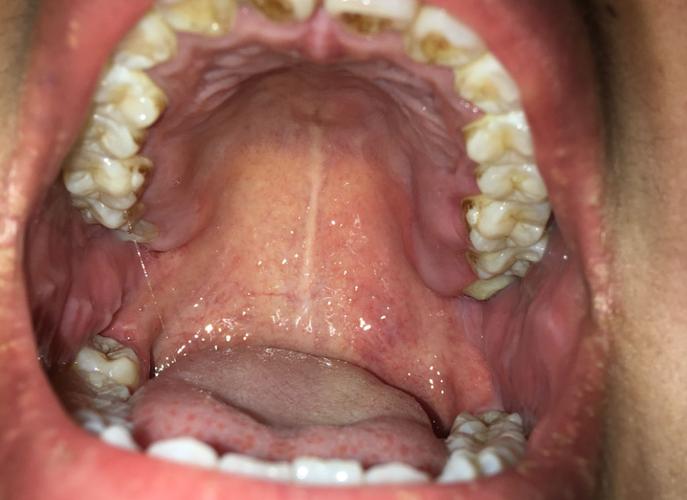

口腔上颚中间白线是啥?正常吗?

您所说的“白线”,在医学上通常被称为腭中线或腭缝线,它并不是一个真正的“缝”,而是上颚(硬腭)左右两块骨头在胚胎发育时融合后留下的痕迹。

- 颜色:通常是白色或浅粉色的,因为它的表面覆盖的是一层角化的复层鳞状上皮,这层皮肤比较坚韧,颜色比周围的口腔黏膜要浅一些。

- 形态:它是一条从门牙(上排正中间的牙齿)后方开始,向后延伸到悬雍垂(小舌头)前方的细长、略微凹陷的线。

- 触感:用舌头轻轻触摸,可以感觉到它是一条微微凸起或凹陷的“沟”或“脊”。

- 常见伴随物:在腭中线的前端(靠近门牙的地方),常常可以看到几个小凸起,这被称为“腭乳头”,是颌下腺和舌下腺导管的开口处,也是正常的生理结构。

口腔上颚中间的白线(腭中线)是完全正常的生理结构,是胚胎发育的痕迹,它通常是一条细长、白色、略微凹陷的线。

如果您只是看到这条线,没有任何疼痛、颜色改变或肿块,就完全不用担心。

但如果这条线的颜色、形态、触感发生了异常变化,或伴有疼痛、出血等症状,建议及时咨询口腔科医生或耳鼻喉科医生进行检查,以排除病理性的可能。